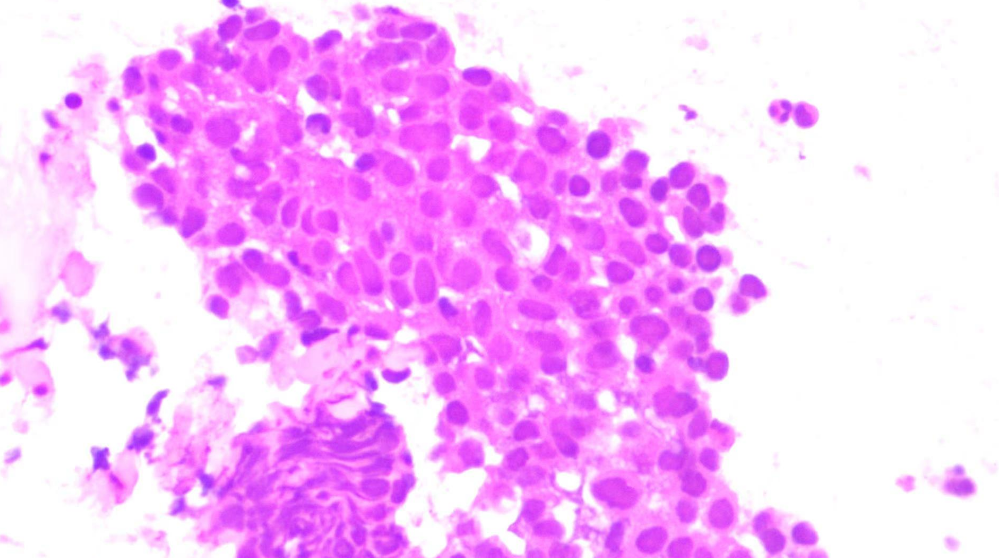

在多学科团队密切配合下,手术顺利完成并成功获取有效组织标本。最终病理结果明确为鼻咽癌转移灶阳性。